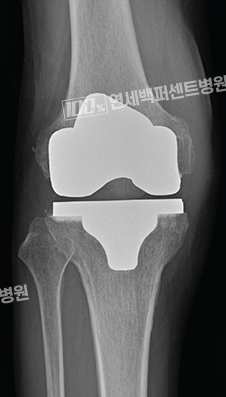

로봇 인공관절수술 중점병원

의사를 가르치는 의사, 마코 로봇수술 교육 지도자 상주